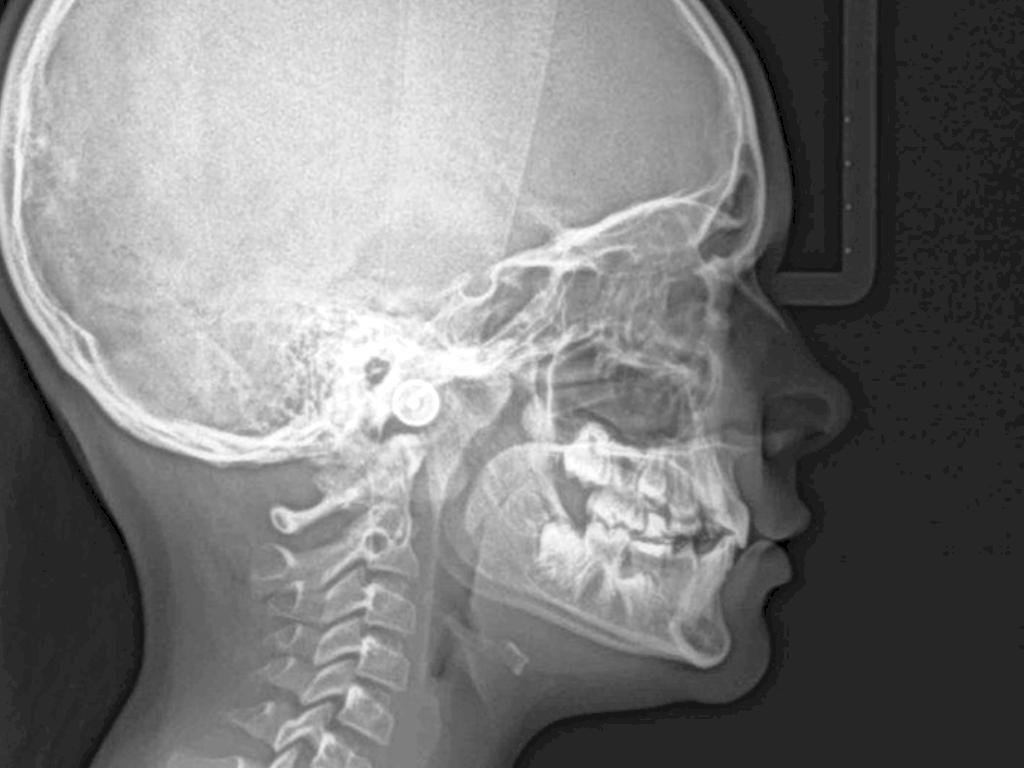

LATERAL

Incisivos proclinados

Clase II

Tercio medio disminuido